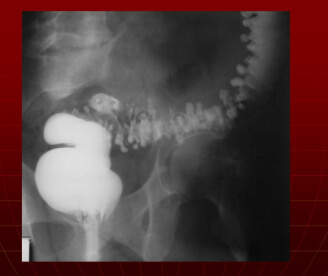

Більшість хвороб можуть призвести до смерті, тому боятися лише раку – це неприпустима помилка. Подивіться знімки органів людей, у яких все почалося з неприємного запаху з рота, сверблячки та кров'янистих виділень із анального отвору відповідно, а закінчилося доповіддю патологоанатома.